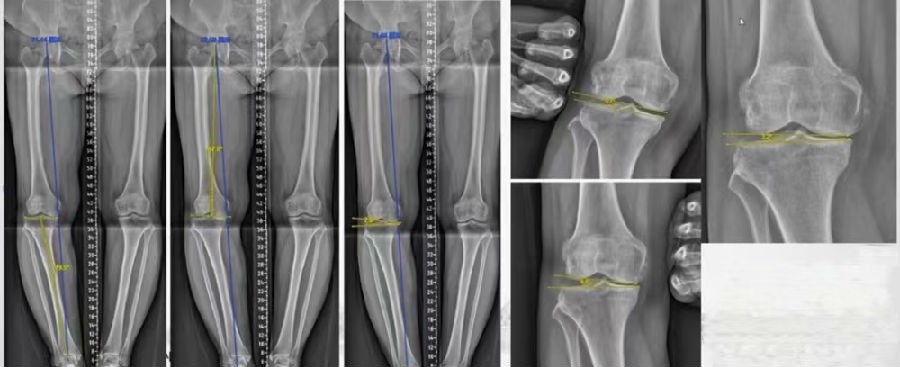

通过MAT测量全长片和内外侧应力位片,可以明确的测量出畸形的来源是股骨还是胫骨,有没有关节内磨损和韧带松弛。

膝MCOA病例,对线异常来源多个因素:胫骨畸形(MPTA异常),股骨形(mLDFA异常),胫骨平台塌陷,LCL松弛,内侧关节软骨丢失造成关节线不等宽等。MAT可以确定其中每种成分;应力下拍片,确定JLCA的关节松弛成分。关节软骨丢失占JLCA 3度,LCL松弛占JLCA 4度。

典型病例,女性,56岁,农民右膝内翻18度。

术前影像